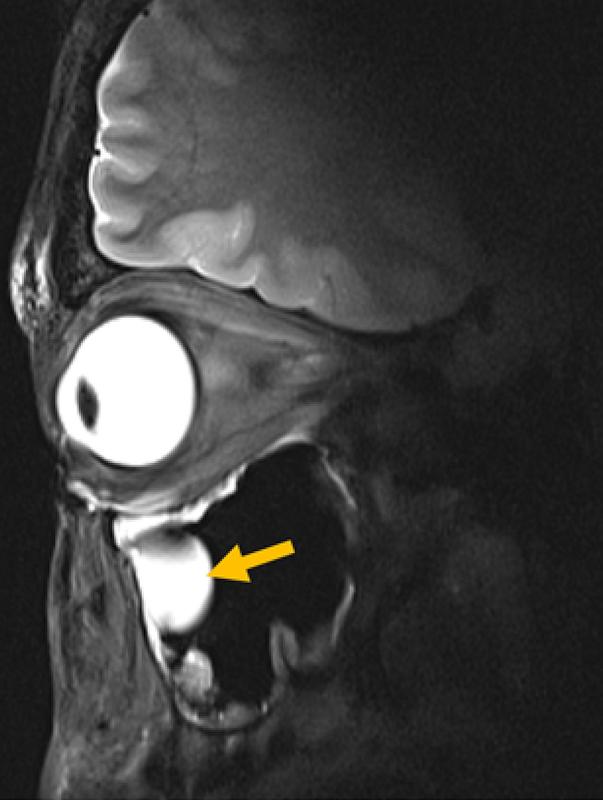

Entscheidend für die klinische Praxis ist zudem, dass die Antenne in bestehende MRT-Systeme passt, sodass keine neue Infrastruktur erforderlich wird. Validiert haben die Wissenschaftler*innen ihre Technologie anhand von MRT-Bildern des Auges, der Augenhöhle und des Gehirns bei einer Gruppe von Freiwilligen. Niendorf und sein Team arbeiteten dabei eng mit Forschenden des Universitätsklinikums Rostock zusammen und kombinierten so Expertise in MRT-Physik mit klinischer Ophthalmologie und translationaler Bildgebung.

Die Forschenden konnten zeigen, dass ihr System für den routinemäßigen klinischen Einsatz geeignet ist. „Wir sehen eine klare Relevanz für Anwendungen in der Augenheilkunde. Die neue Technologie ermöglicht anatomisch detaillierte MRT-Bilder des Auges mit hoher räumlicher Auflösung und Weichteilkontrast“, sagt Professor Oliver Stachs, Koautor der Publikation von der Universitätsmedizin Rostock. „Sie öffnet die Sicht auf (patho)physiologische Prozesse, die bislang weitgehend unzugänglich waren.“